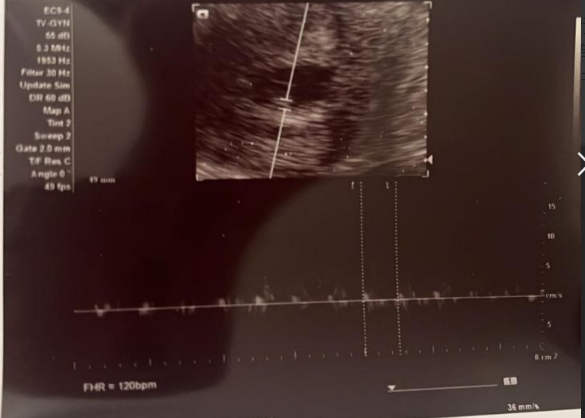

1月24日、妊娠7週。胎児の心拍を無事に確認できました。

小さな鼓動が確かに感じられ、

新しい命からの最初のメッセージを受け取ることができました。

今回の経過確認も順調で、母体の状態も良好です。